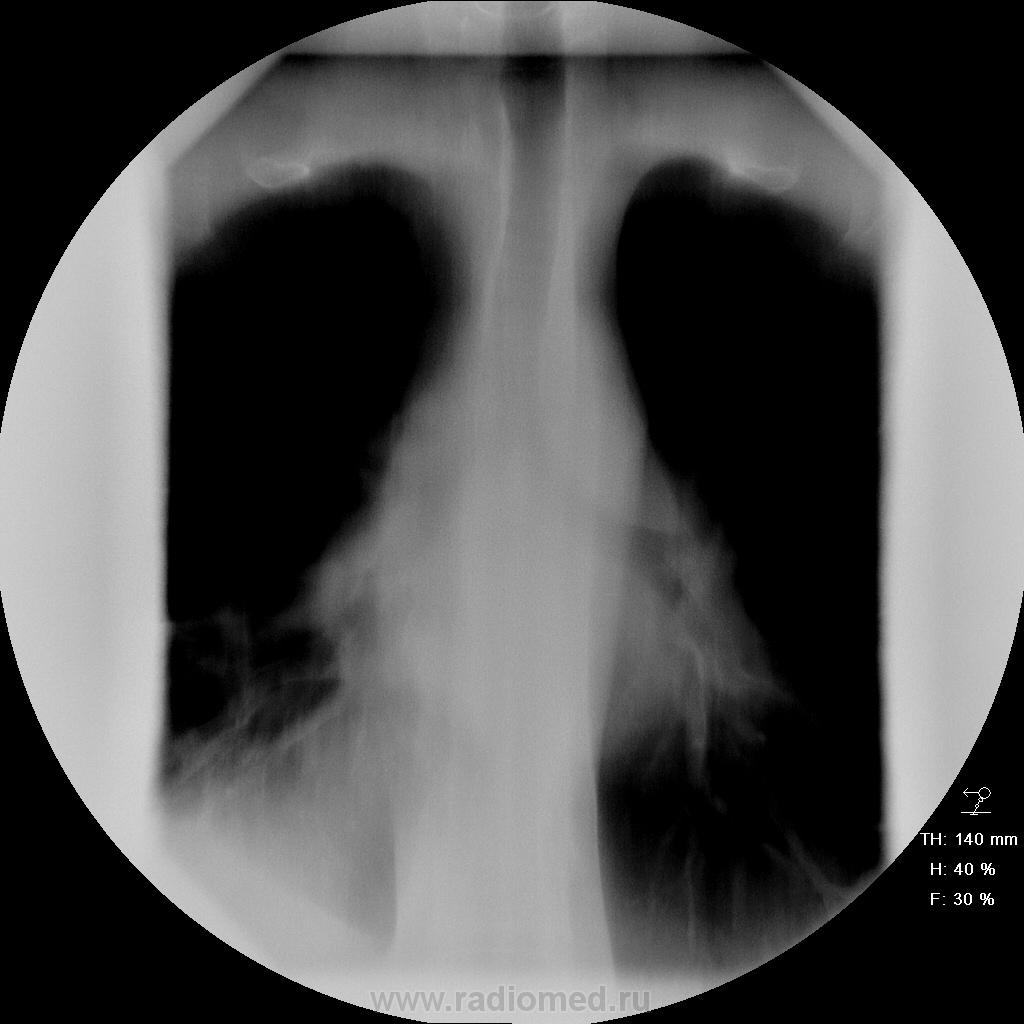

Пациент поступил в пульмонологию с диагнозом" пневмония". Т до 41, кашель, мокрота(иногда с кровью), боли в грудной клетки справа, высокое СОЭ, и т.д. Не худел. Год назад рожистое воспаление ноги, СД.

Поступил 6.01.10. была произведена обзорная р-грамма легких, по картине схожая со снимками от 13.01.10

Правостороння н\долевая деструктивная пневмония, в динамике осложнившаяся междолевым (по ходу косой щели) и базальным (у основания косой щели) осумковаными плевритами.

Коллеги, вы правильно последовательность снимков смотрите? stovbav , почему деструктивная? по клинике гораздо лучше. При последнем исследовании (от28.01.10 - серия томо+ обзорный и правый бок) на мой взгляд - уменьшение объема нижней доли, участки инфильтрации, больше в S6,следы жидкости. Формирование цирротических изменний(пневмосклероза)Меня смутило - уменьшение объема. Проходимость нижнедолевого не нарушена? еще терапевты спрашивают можно ли выписать с такими изменениями? еще в праве ли мы советовать клиницистам вообще о сроке выписке пациентов? частенько изменения на снимках есть, а человек чувствует себя замечательно, и по срокам все отлежал, а хотят выписать. что в таких случаях говорить клиницистам? какие ваши мнения?

Разве на томограммах в С10 и С6 не полости распада? Тогда что это? Так причудливо сумируются тени рубцов? И разве не могут быть дренированые абсцессы исходом пневмонии?

Согласен на томограммах видны 2-3 полости распада, а ещё осумкованный паракостальный плевральный экссудат на задней стенке (он виден и 22.01).

На мой взгляд имеет место нижнедолевая абсцессдирующая пневмония, затяжное течение. Плеврит имел место, но вот на счет осумкования, категорически не согласен, т.к. выражненная перисциссуальная инфильтрация и дала эту симуляцию. То, что в данный момент объективное сосотояние не соответствует томографической картине - полости деструкции, уплотнение легочной ткани пербронхиального преимущественно характера говорит лишь о том, что купирована лишь острая фаза воспалительного процесса. Необходимо продолжить терапию в том числе и против формирования фиброзной ткани.